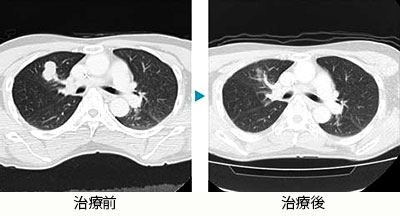

- 転移性肺がん(直腸がん)

転移性腫瘍

転移性腫瘍(治療前)

転移性腫瘍(治療後)

転移性肺がん(直腸がん)